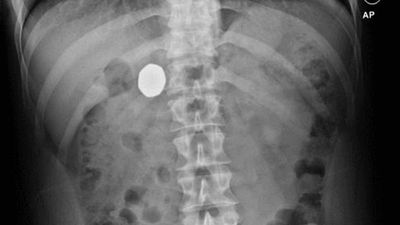

Një burrë gëlltiti aksidentalisht dy monedha metalike pasi shokët e tij i vunë ato në birrën e tij për shaka.

Megjithatë, monedha tjetër metalike, e cila është rreth 2.5 cm e gjerë, qëndroi brenda trupit të tij për të paktën dhjetë javë.

Kirurgët zbuluan se rreziku i ndërlikimeve nga kirurgjia ishte më i madh se rreziqet për të lënë monedhën brenda trupit.